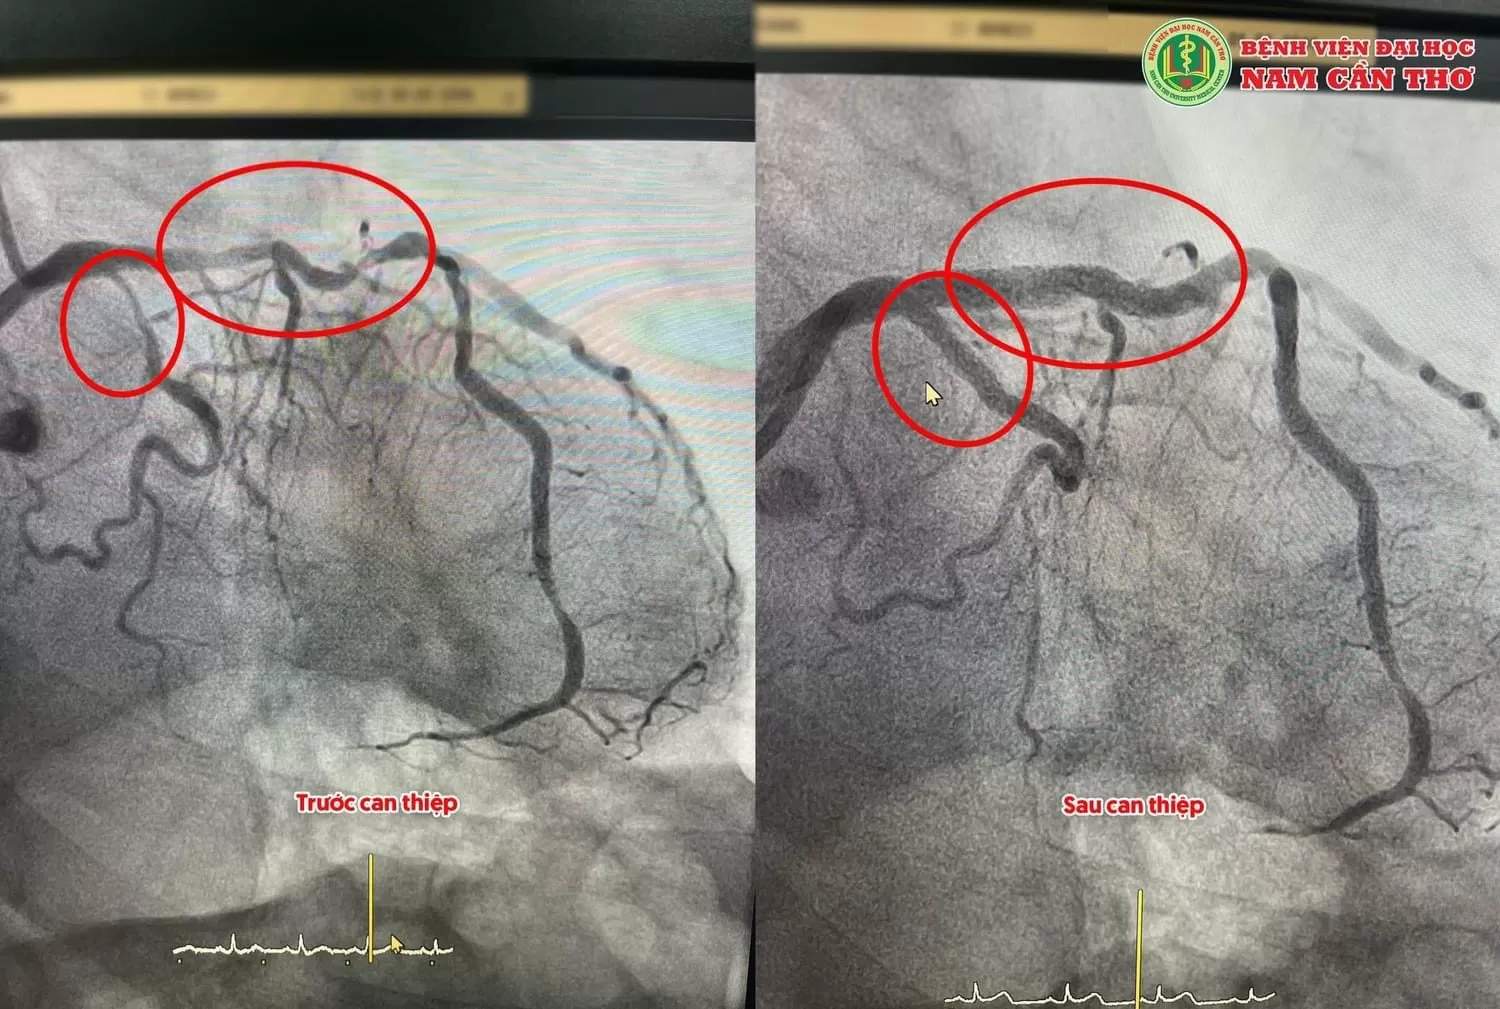

Với kinh nghiệm nhiều năm làm trong lĩnh vực can thiệp tim mạch và can thiệp tim mạch cho hơn 7.000 bệnh nhân. Bác sĩ Trần Chí Dũng can thiệp cho nhiều bệnh nhân cấp cứu trong tình trạng nguy kịch, nhồi máu cơ tim có những tổn thương mạch vành phức tạp, ngay cả hẹp nặng những góc động mạch vành cũng đã được cứu sống như: trường hợp bệnh nhân nam 50 tuổi, bị nhồi máu cơ tim cấp thành trước, bị tắc nhánh LAD (nhánh chính) rất lớn và dài đã được can thiệp mạch vành, bệnh nhân được đặt 1 stent vào nhánh LAD mạch máu tái thông hoàn toàn. Một yếu tố đặc biệt, bệnh nhân thường xuyên sử dụng thuốc lá và có yếu tố thừa cân. Hiện tại, bệnh nhân đã qua cơn nguy hiểm và sức khỏe đang dần ổn định trở lại.

Một trường hợp nữa là cụ ông 80 tuổi, bị nhồi máu cơ tim cấp không ST chênh lên. Ông bị hẹp nặng 2 mạch máu chính. Nhánh LAD hẹp dài lần tỏa, Calci hóa nặng, mạch máu xoắn vặn. Nhánh LCx hẹp nặng từ lỗ xuất phát. Ông được can thiệp đặt 3 stent (2 stent LAD, 1 stent LCx) mạch máu tái thông hoàn toàn.

Còn trường hợp một bệnh nhân Nam 68 tuổi Bị nhồi máu cơ tim cấp, bệnh nhân bị hẹp nặng ngay gốc động mạch vành, hẹp nặng dài lan tỏa 2 nhánh chính động mạch vành, tình trạng rất nguy kịch, cũng được BS CKII Trần Chí Dũng và ekip can thiệp đặt 3 stent LM – LAD, LM-LCXI, LCxI-II mạch máu tái thông hoàn toàn, bệnh nhân đã qua cơ nguy kịch.